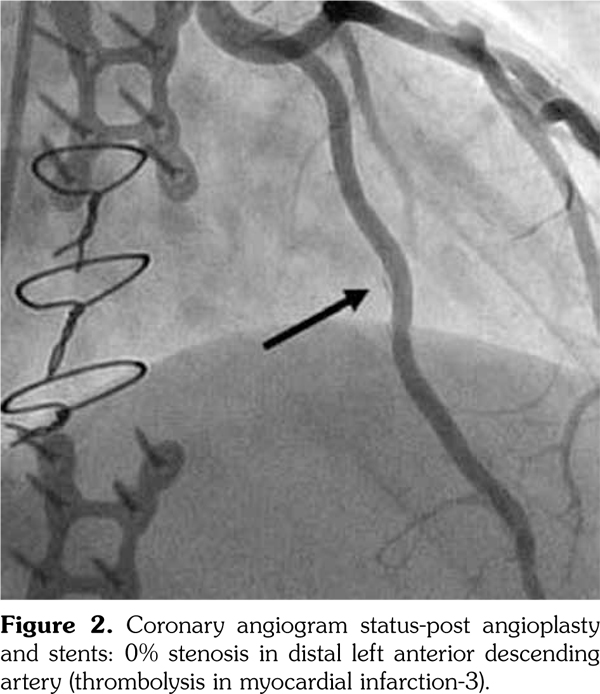

On admission, troponin was 0.05 ng/mL and electrocardiogram revealed sinus tachycardia with peaked T-waves in leads I, aVL, and V5-V6; and inverted T-waves in leads III and aVF. Echocardiogram demonstrated left ventricular hypertrophy with an ejection fraction of 55%. Selective coronary angiography (Figure 1) disclosed a 70% stenosis of the left internal mammary artery graft to the left anterior descending coronary artery and a 99% stenosis in the distal left anterior descending artery. Patient was treated with coronary angioplasty and two drug-eluting stents, reducing stenoses to 0% per final angiography (Figure 2).